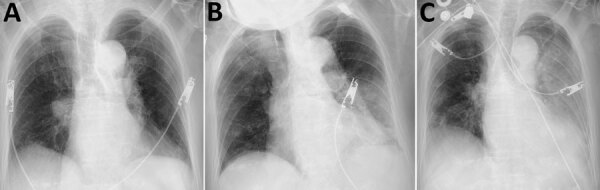

Description:A patient in Japan with coronavirus disease and hypervirulent Klebsiella pneumoniae K2 sequence type 86 infection died of respiratory failure. Bacterial and fungal co-infections caused by region-endemic pathogens, including hypervirulent K. pneumoniae in eastern Asia, should be included in the differential diagnosis of coronavirus disease patients with acutely deteriorating condition.